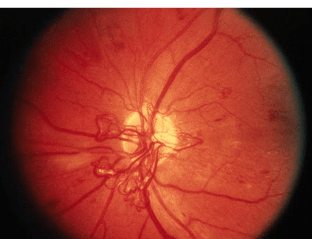

2. PDR (Proliferative Diabetic Retinopathy)

PDR is the more advanced stage of diabetic retinopathy.

- The retina starts growing new blood vessels: a process called neovascularisation

- These fragile new vessels often bleed within the eye called: vitreous haemorrhage

- If they only bleed a little, you might see a few floaters.

- If they bleed a lot, vision may be blocked.

Abnormal blood vessels

Abnormal bleeding in eye